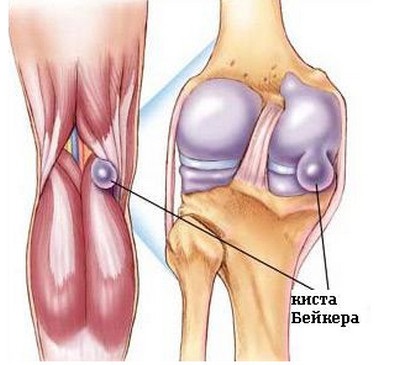

Térd oszteoartritisz szindrómái

Leggyakrabban szenvednek az ízületek, amelyek a legnagyobb terhet jelentették. Felismerik, hogy a betegség eredete abban az esetben fordulhat elő, ha a terhelés után, a gravitáció felemelése és a régóta fennálló fájdalom, az éjszaka közepéig fennáll a fájdalom. A beültetett osteoarthritis esetén a fájdalom a séta kezdetén jelentkezik, majd elhalványul. Amikor a megsemmisült porc a csontok felszínén megy keresztül, egy piercing fájdalom van.

Gyakrabban, mint a férfiak, a nők kialakítják a kéz ízületeinek osteoarthritisát. Rendszerint ez nem jár fájdalmakkal, de a vizenyős váladék megvastagodása vizuálisan észrevehető. Ajánljuk a paraffin fürdőket. Egyébként a dolgok a térdben vannak. Ebben az esetben a térdízületi tünetek osteoarthritis sokkal komolyabb.

Leggyakrabban idős emberek. És a mítosz, hogy a legegészségesebb emberek - a sportolók, már rég eloszlottak. Az ő esetükben, erős fizikai erőfeszítéssel - ez egy professzionális betegség. Így a térd osteoarthritis számos tünete:

- kellemetlen érzés a térdben hosszú sétát vagy hosszan tartó állást követően,

- fájdalom a megnövelt terhelésektől,

- a szokásos terhelésekkel, a gyors fáradtságérzéssel,

- "Kezdet fájdalommal" reggel,

- nyugalomban, a fájdalom eltűnik, de nem megy el,

- jellegzetes csomó a kötésben mozgás közben,

- éles fájdalom az ízületben,

- amikor fájdalmat érzett a térdben,

- ödéma vagy látható deformitás.

A betegség színpadának meghatározásához röntgenfelvételt kell készíteni, és számos tesztet kell elvégeznie. Az elsődleges feladat a fájdalom eltávolítása. Ezután az erők rohanni kezdik a porc és a motor működésének helyreállítása érdekében. A kondroitint és kollagént tartalmazó termékek nagyon hasznosak. A chondroitin bőséges a tenger gyümölcseiben.

Masszázs, akupunktúra, fizioterápia, terápiás torna - mindez hatékony kiegészítő intézkedések. A térdízületi betegségek elleni küzdelem nem könnyű feladat, de a kitartás és a pozitív kimenetelű hit nagyban hozzájárul. Fontos, hogy az osteoarthritist korai stádiumban ismerjék el annak érdekében, hogy a betegséget ne hozzák a fogyatékosság állapotába, amikor a mesterséges ízületi implantációt már használják.